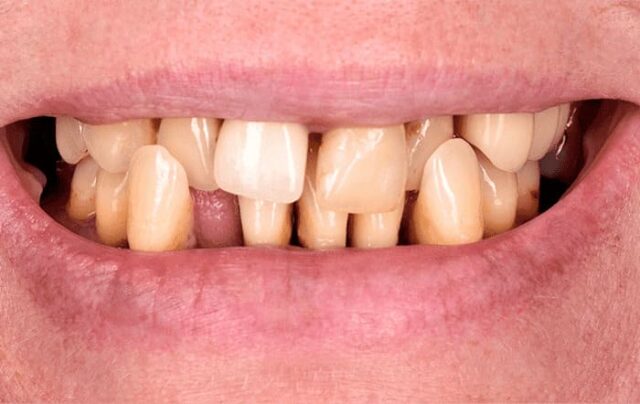

Экстракцию зубов выполняют по многим причинам — при сильной подвижности, переломе корня, неправильном положении, сверхкомплектности и т.д. Бывает, что после удаления нерва зуба под коронкой развивается кариес, и если обнаружить его слишком поздно, орган трудно сохранить.